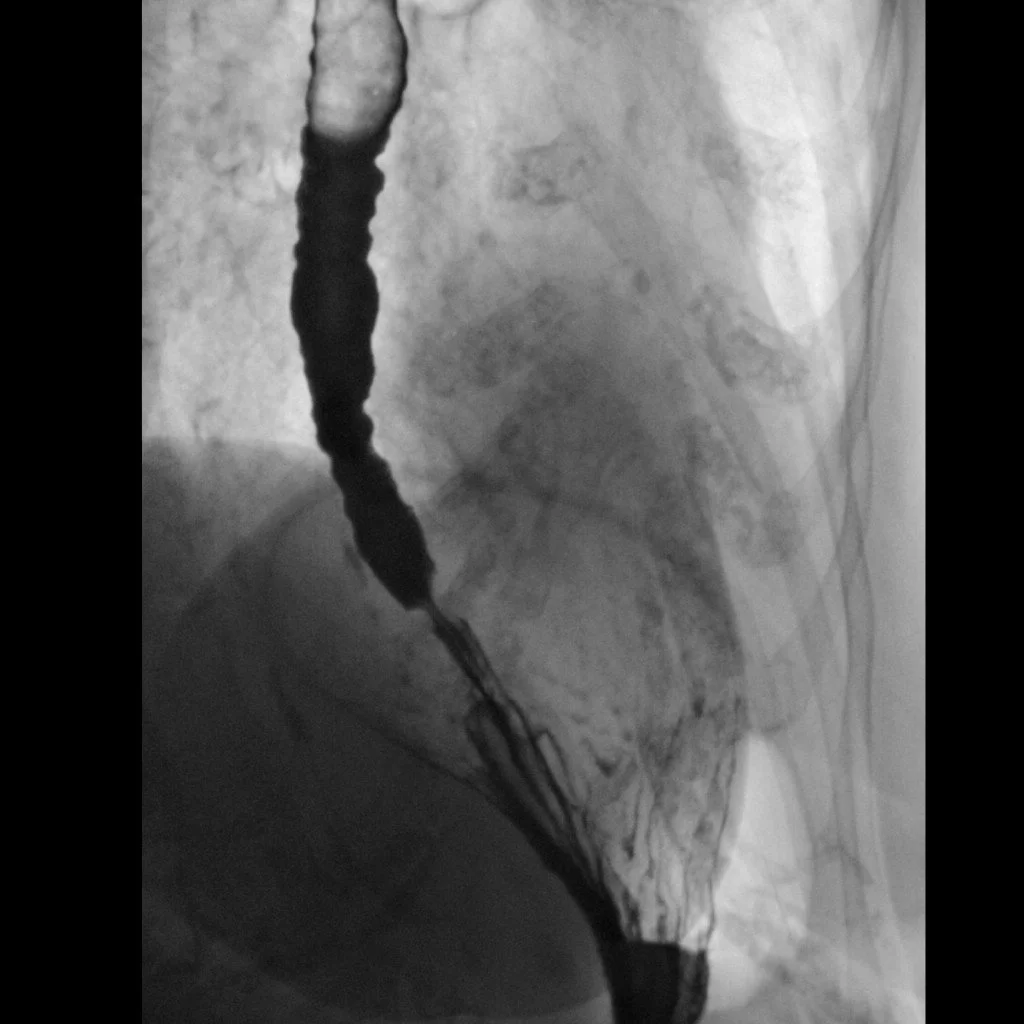

Feline esophagus